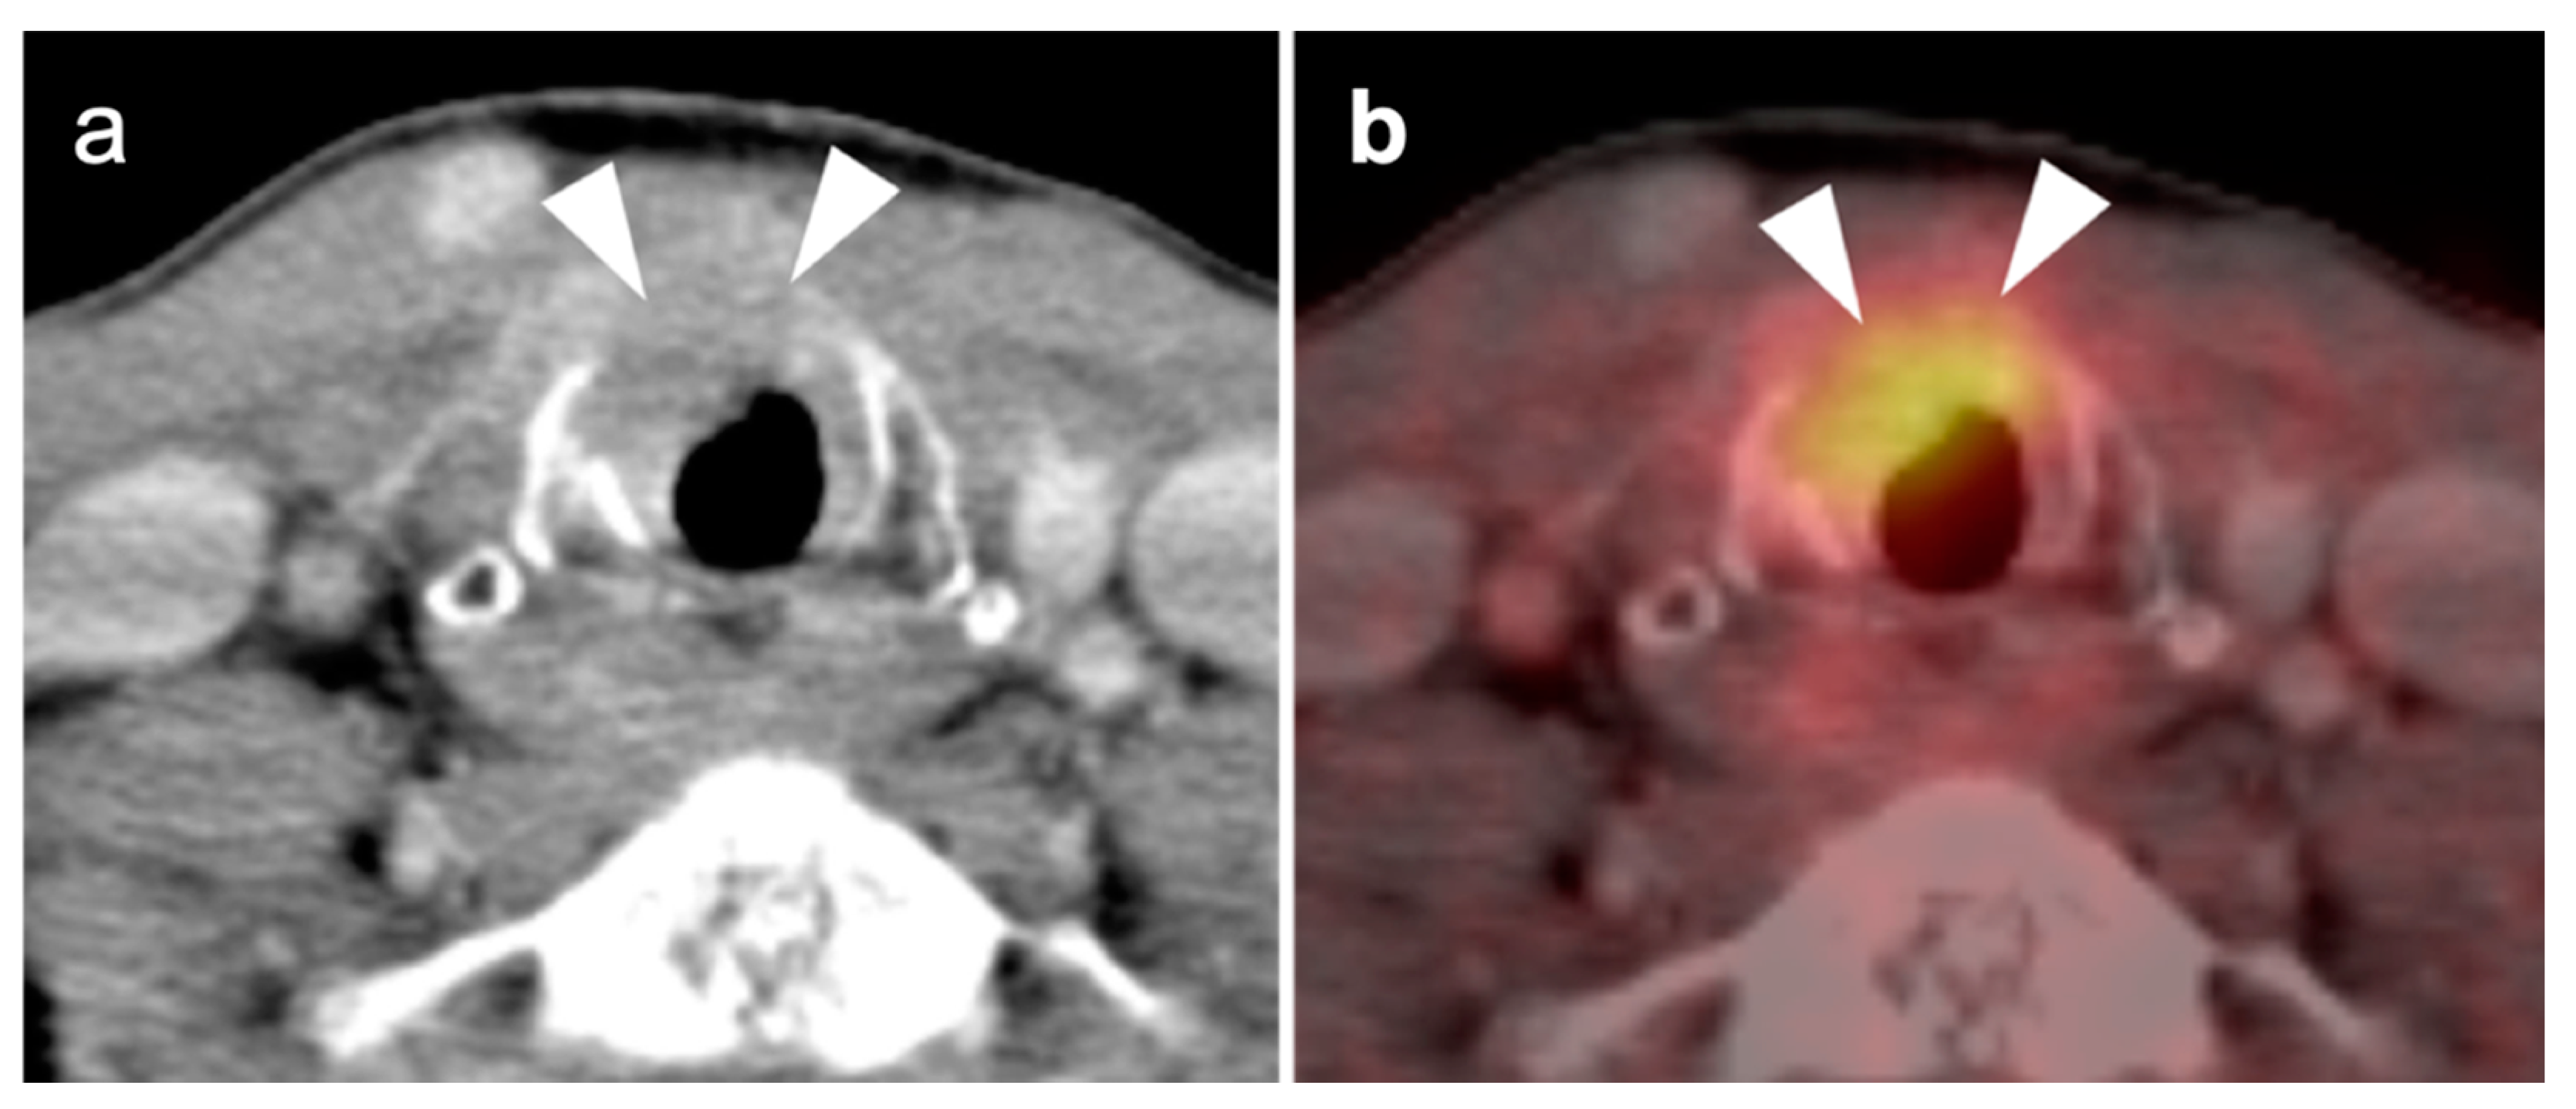

2.2. Squamous Cell Carcinoma of the Head and Neck (SCCHN)

- Hypopharyngeal squamous cell carcinoma

- Laryngeal squamous cell carcinoma